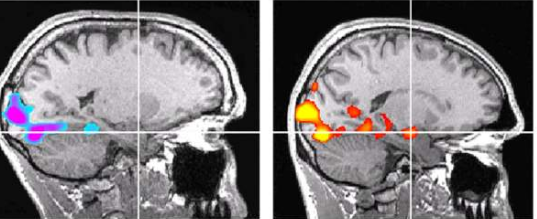

(실제로 알렉스는 일반인과 뇌구조부터 다르다고 한다. 알렉스의 뇌에서는 공포를 느끼는 편도체의 활동이 감지되지 않는다나? )